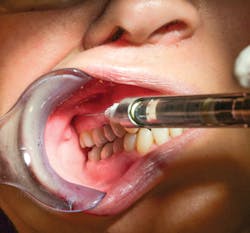

The needle, with the bevel oriented away from the bone of the mandibular ramus so it faces toward the midline, is directed medially past the coronoid process and then inserted into the buccal mucosa at the established height. The needle is then advanced posteriorly and slightly laterally without contacting the medial surface of the bone of the mandibular ramus unlike the IA block, with the hub of the syringe ending up opposite the mesial aspect of the maxillary second molar (see Figure 7). The needle will naturally deflect toward the mandibular ramus so that the needle will remain in close proximity to the IA nerve for the highest level of clinical effectiveness.2,3,4

Due to the closed-mouth situation, it may be difficult to visualize the path of the needle, so depth of the needle is always a concern and must be carefully controlled; the depth is approximately half the mesiodistal length of the mandibular ramus as measured from the maxillary tuberosity (see next discussion). The depth of insertion is approximately 25 mm or two-thirds to three-fourths of a long needle for the average-sized adult with the distance measured from the maxillary tuberosity; in smaller or larger patients, this depth of penetration should be adjusted to more or less (see Figure 8).3,4 Thus the depth of insertion will vary with the anteroposterior size of the patient's mandibular ramus.2,3,4

Figure 7: Needle insertion during a Vazirani-Akinosi mandibular block at the buccal mucosa between the bony surfaces of the medial surface of the mandibular ramus and the maxillary tuberosity, with the syringe barrel parallel to the maxillary occlusal plane. The needle was first directed medially past the coronoid process. The exact insertion point is hard to discern due to buccal frenum interference. The needle is advanced posteriorly and slightly laterally without contacting the medial surface of the mandibular ramus, and with the hub of the syringe ending up opposite the mesial aspect of the maxillary second molar. The syringe is stabilized by the clinician resting the pinky of the dominant hand on the patient's chin.2,3 (courtesy of Elsevier)